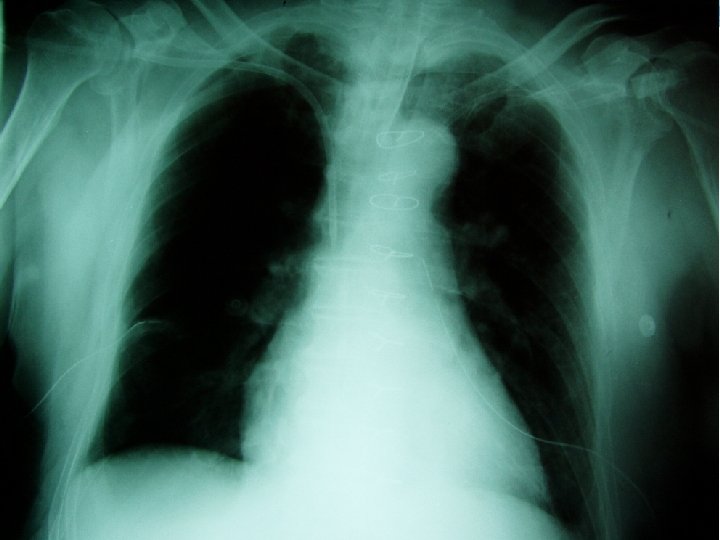

Central venous catheter - What to do after cannulation sterile cover control chest X-ray exclude PNO check position of catheter

Central venous catheter - Complications arythmias PNO bleeding punction of arteria damage of plexus brachialis air emboly thrombosis (v. femoralis) infection, sepsis